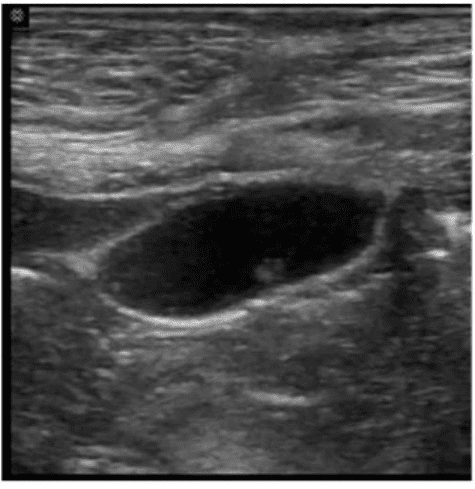

Which sonographic appearance of the bile ducts is demonstrated in this image?